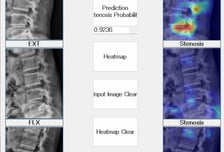

MRI 없이 진단 어려운 요추협착증, '정확도 91.4%' 엑스레이로 찾는다

서울대병원 연구팀은 최근 다중 자세(중립·굴곡·신전)에서 촬영된 허리 X선(엑스레이) 사진을 기반으로 한 인공지능 모델을 개발했다고 2일 발표했다. 이 모델은 MRI(자기공명영상)를 사용하지 않고, X선 사진만으로 91.4%의 진단 성능을 기록하며 요추협착증을 정확히 진단할 수 있는 가능성을 보여줬다. 향후 이 모델은 MRI 비용 절감과 의료 접근성 향상에 중요한 기여를 할 수 있을 것으로 기대된다. 요추협착증은 척추관이 좁아져 신경을 압박하는 질환으로, 하반신에 통증·무감각·약화 등의 증상으로 나타난다. 주로 노년층에서 발생하며, 증상이 앉거나 걷는 동안 심해진다. 기존 MRI는 요추협착증 진단에 가장 정확하지만, 고가의 검사비, 긴 촬영 시간, 중대형병원에서만 촬영할 수 있다. 반면 X선 촬영은 저렴하고, 빠르며, 차량으로 이동식 촬영도 가능하지만, 진단 성능은 매우 낮았다. 이에 서울대병원 신경외과 이창현 교수 연구팀은 2005~2017년 촬영된 요추협착증 환자 2500명과